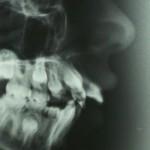

Negli anni successivi al trauma il paziente andrà controllato periodicamente per verificare, attraverso radiografie e tests di vitalità, che il nervo sia sempre vivo e non si stiano instaurando fenomeni degenerativi; cambiamenti di colore, ascessi e anchilosi sono evenienze negative che possono presentarsi anche a distanza di molti anni dal trauma.

I denti permanenti invece vedono tra le cause più frequenti le attività sportive (importante l’uso di paradenti sportivi individualizzati, foto 3), le anomalie dento-scheletriche che comportano aumento di overjet (foto 4 e 5) e gli incidenti stradali.

Foto 5